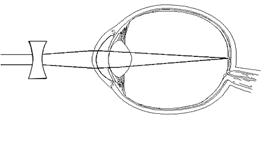

Aus physikalischer Sicht wird ein Gegenstand für uns sichtbar, wenn das von einer Lichtquelle (z.B. Sonne, Lampe) ausgestrahlte Licht von diesem Gegenstand reflektiert wird. Diese reflektierten Lichtstrahlen werden in der Linse des Auges gebündelt, sodass auf der Netzhautmitte ein scharfes Bild entsteht. Das entstandene Bild steht auf dem Kopf. Die Lichtstrahlen treffen auf die Zapfen der Netzhaut. Die Informationen, die bei jedem Zapfen entstehen, so genannte elektrische Nervenimpulse, werden im gelben Fleck gesammelt und über den blinden Fleck an das Gehirn weitergeleitet. Dort entsteht das richtige Bild. (Abb1)

Auf der Bild 1 sieht man den Querschnitt eines Auges, das gerade einen Gegenstand fokussiert.

Abb1: Der Apfel reflektierten

Lichtstrahlen, die in der Linse des Auges gebündelt werden, sodass auf der

Netzhautmitte ein scharfes Bild entsteht. Das entstandene Bild steht auf

dem Kopf. Die Lichtstrahlen treffen auf die Zapfen der Netzhaut. Die

Informationen, die bei jedem Zapfen entstehen, die so genannte elektrische

Nervenimpulse, werden im gelben Fleck gesammelt und über den blinden Fleck

an das Gehirn weitergeleitet. Dort entsteht das richtige Bild.

Bild 1: Titel des Bildes, aus: Microsoft Corporation 2000, Suchbegriff: Auge.